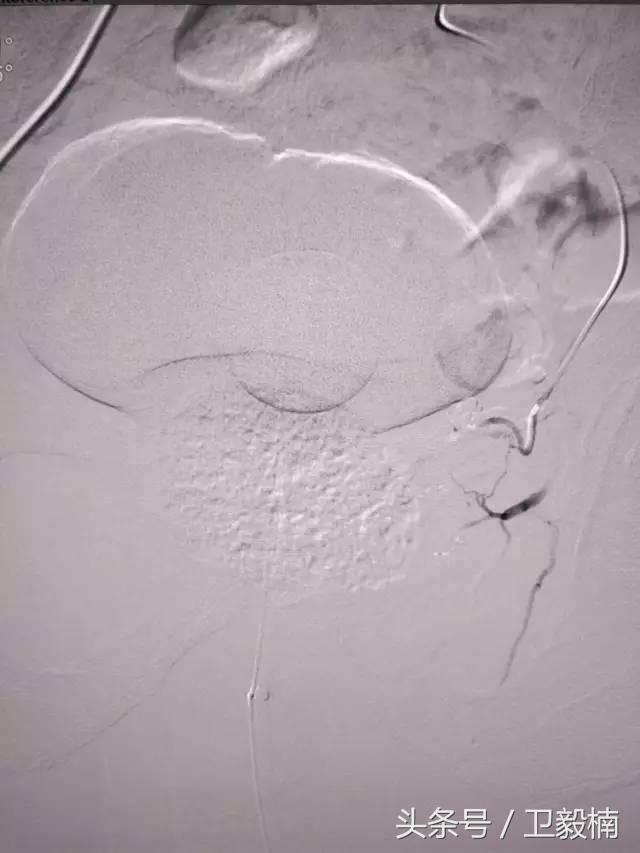

二、各类肿瘤的治疗:如肝癌、肺癌、食管癌、肾癌、胰腺癌、各种转移性肿瘤及妇科肿瘤、骨肿瘤等;

三、肝血管瘤栓塞术、肾错构瘤栓塞术和肝、肾囊肿、脓肿抽吸硬化术等;

(1)选择性肿瘤供血动脉灌注化疗+栓塞治疗恶性肿瘤。

(3)应用栓塞术治疗海绵状血管瘤,蔓状血管瘤,子宫肌瘤,骨肉瘤,鼻咽部纤维血管瘤等。

(4)热消融治疗肝癌,肺癌。